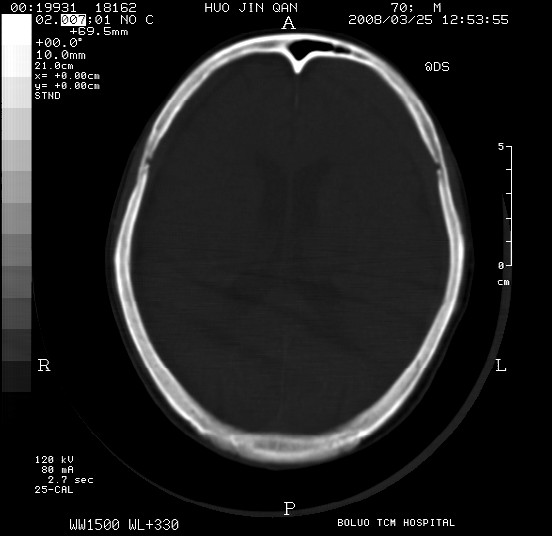

以下是引用随光逐影在2008-3-25 20:15:00的发言:[br]双侧额颞顶部亚急性(或慢性)硬膜下血肿。

以下是引用liuyue在2008-3-26 18:57:00的发言:[br]以下是引用随光逐影在2008-3-25 20:15:00的发言:[br]双侧额颞顶部亚急性(或慢性)硬膜下血肿。 [br]支持![br]可以无明显外伤病史,老年人可以在激烈摇晃或轻微头部碰创头部时,发生硬膜下出血.